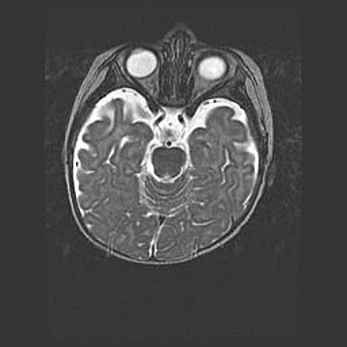

Церебральная ишемия II.

Возраст: 5 дней

Вес: 3400 г

Пол: женский

Окружность головы: 35 см

Срок гестации: 39 недель

Церебральная ишемия – это заболевание, характеризующееся недостаточностью (гипоксией) либо полным прекращением (аноксией) снабжения мозга кислородом по причине закупорки одного или нескольких сосудов. Это приводит к  что метаболическим расстройствам различной степени тяжести в тканях головного мозга, развитию коагуляционных некрозов и гибели нейронов.